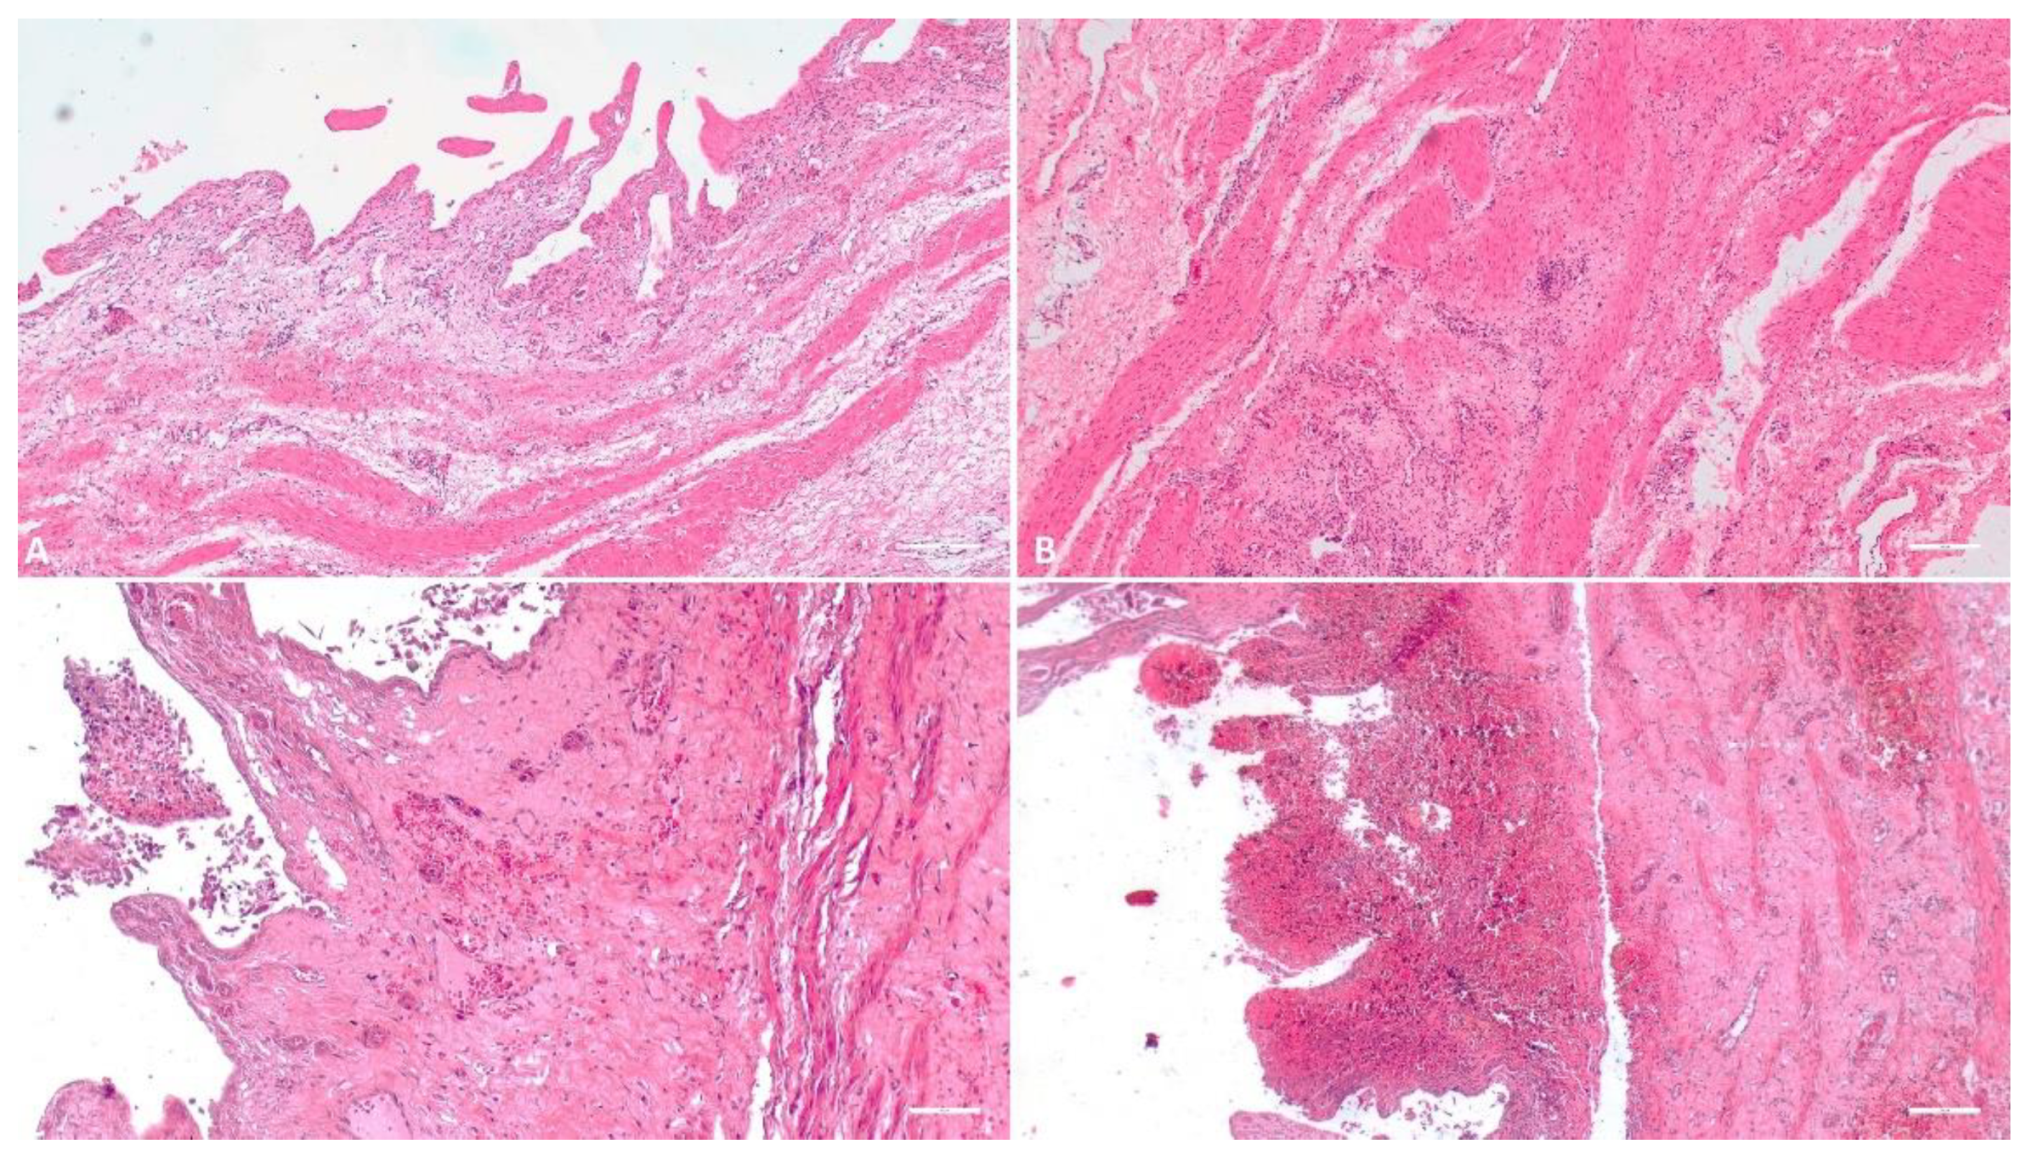

3.1.1. Kidney

3.1.2. Liver

3.1.3. Gallbladder

3.1.4. Spleen

3.1.5. Lymph Node

3.1.6. Heart

3.1.7. Lung

3.1.8. Tonsil